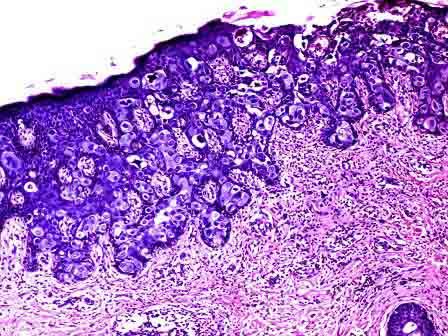

问题 女性,30岁,乳头呈湿疹样。手术切除,镜下表皮内可见非典型细胞增生,细胞呈小簇状分布,中央密集(如图)。最有可能的诊断为 ( )

选项 A.乳头派杰病 B.恶性黑色素瘤 C.鳞癌 D.乳头腺瘤 E.汗管瘤样腺瘤

答案 A